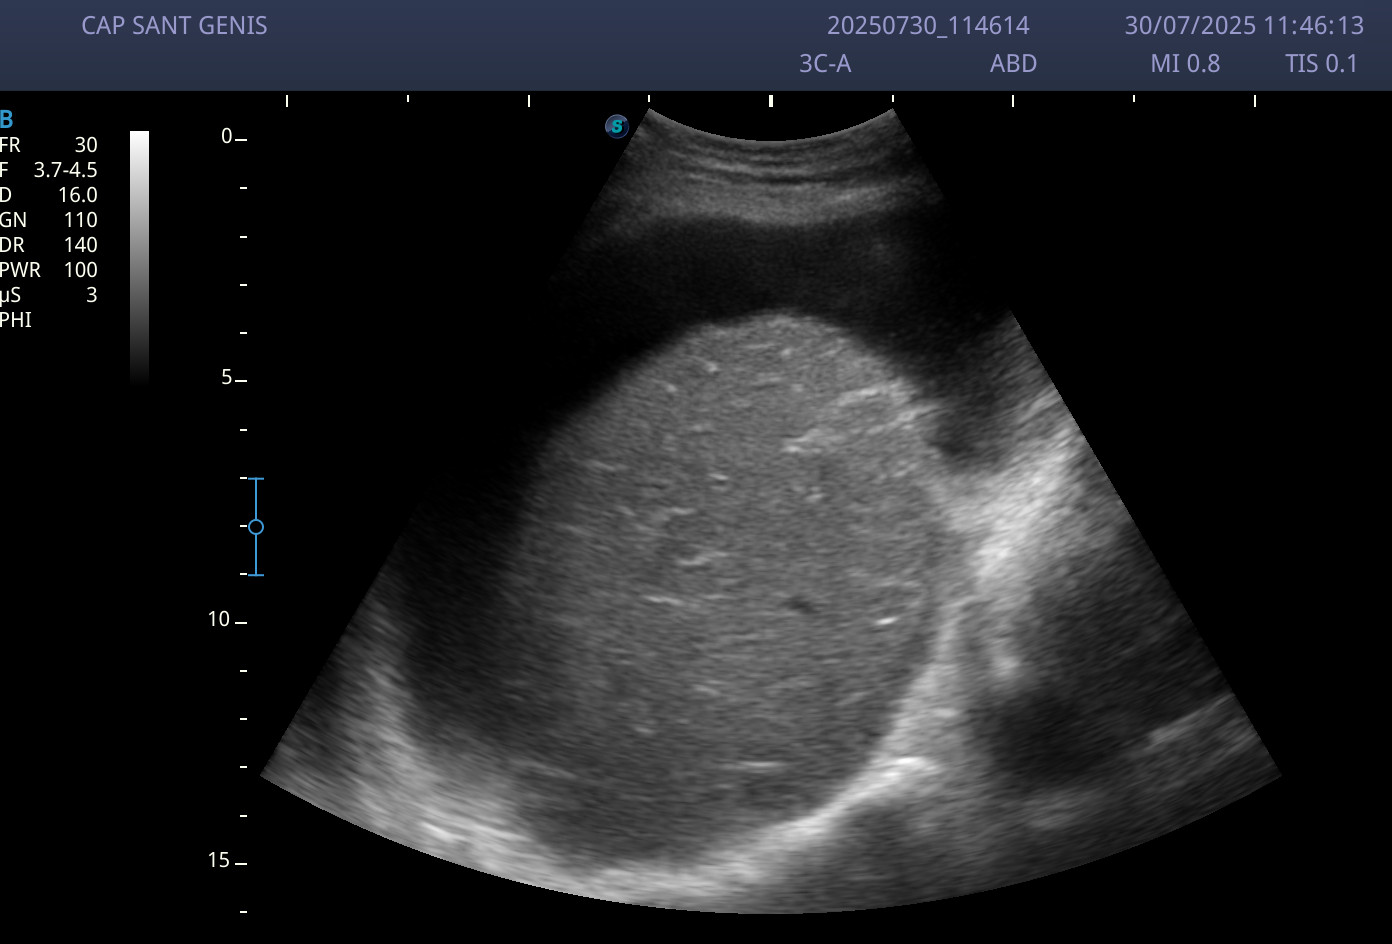

Ecografía abdominal: abundante ascitis perivisceral, y sobre todo a nivel perihepático.